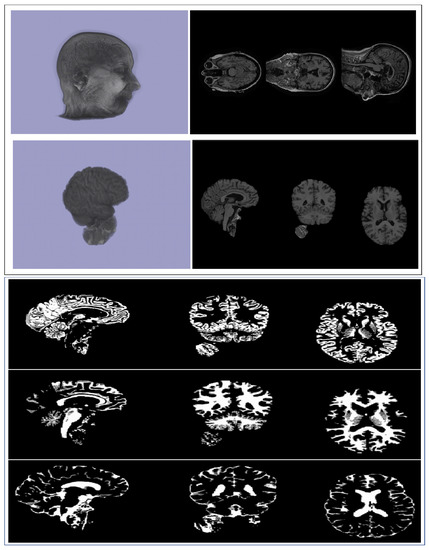

We used Brain Extraction Tools (BET) [24] to extract the usable brain images. BET is a part of the well-known FMRIB (Functional Magnetic Resonance Imaging of Brain) Software Library (FSL) [25], which contains tools for image and statistical analysis for functional, structural, and diffusion MRI brain imaging data. Using BET, we deleted non-tissue regions from an image of the whole-brain structure (Figure 1, Left). In the whole image, a large number of voxels are zero. This is expected, as the brain is in a more centrally enclosed part of the image. Considering this fact and to minimize the computational cost, we removed the encompassing regions with no information contained. Finally, an image acquisition matrix of dimensions 155 × 155 × 95 was used in further studies.

We applied FMRIB Automated Segmentation Tool (FAST) [37] in the FSL software package to obtain individual 3D images corresponding to three tissue types, namely, gray matter (GM), white matter (WM), and cerebrospinal fluid (CSF) (Figure 1, Right). Further, we carried out CNN-based feature extraction and then GWASs on these segmented images similar to those discussed for whole-brain and multi-branch structures.

Figure 1. (Top row) An original MRI image and the corresponding axial views. (Second row) Brain image extracted using BET tool and its axial views. (Bottom three rows) Segmentation of the extracted brain image using FAST; from top to bottom: gray matter (GM), white matter (WM), and cerebrospinal fluid (CSF) images, respectively.